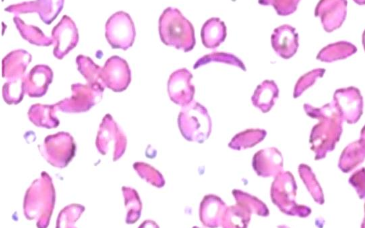

A 20 years old male comes with fever since 5 days. Fever is episodic. The peripheral blood film is shown below.

What abnormality (Micrograph name) do you see in this smear?

- Ring form - Malarial parasite inside RBCs Z

What is your diagnosis?

- Malaria